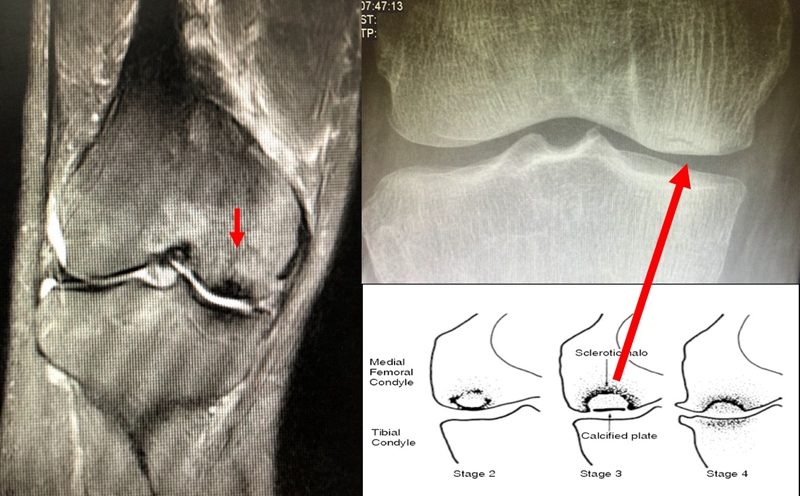

目前SONK诊断最常用的分期方法是1979年Koshino提出的分期法。Koshino分期基于临床和影像学的结果,将SONK分为四个阶段:

Ⅰ期:患者有膝关节症状,但影像学正常;

Ⅱ期:X线显示负重区变平,软骨下信号升高,周围有骨硬化;

Ⅲ期:受影响区域扩大和软骨下塌陷;

Ⅳ期:病变周围骨硬化和髁突周围骨赘形成的退行性阶段。

1979年Koshino分期

关于影像学评估与SONK的预后的关系,多项研究表明小于3.5cm2的小坏死病变可进行保守治疗,在冠状位X片上5cm2软骨下病变面积作为预测预后不良和高风险进展的临界值,前后位X片坏死区>50%髁,会迅速塌陷,病变范围很大(>40%髁/前后位X 片)或有早期骨关节炎的影像表现,保守欠佳。

早期(3月内)内侧半月板相对挤压百分比≥33%,是SONK发病1年后预后不良的预测指标,MRI检查没有局灶性轮廓塌陷和髁深处没有低信号线(隔离带),预后好,股胫角>180°(下肢力线内翻>6°)和MRI上深度>20mm 预示SONK患者症状发作后1年预后不良。